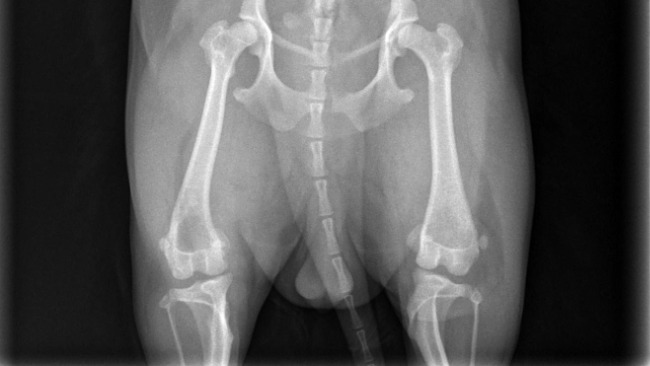

Każde z tych zwierzątek to dla mnie członek rodziny, moje codzienne wsparcie i ogromna radość. Niestety, los nie był Lady dla łaskawy. Zdiagnozowano u niej chorobę ganetyczną, obustronne zwichnięcie przyśrodkowe rzepek II stopnia w obu tylnych łapkach.

Oznacza to, że każdy krok sprawia jej ból. Czasem podnosi łapki, unika chodzenia i piszczy z bólu, a ja widzę, jak bardzo się męczy… 💔

Lekarze jasno powiedzieli, że bez operacji jej stan będzie się pogarszał. W każdej chwili jej tylne łapki mogą stać się całkowicie niesprawne… To myśl, która łamie mi serce.

Jedyną szansą na normalne życie bez bólu i ograniczeń jest operacja obu tylnych łapek, trzeba je złamać, odpowiednio ustawić i ustabilizować. Szacowany koszt zabiegu to około 15 000 zł, dodatkowo koszty rehabilitacji i leczenia, co niestety przekracza moje możliwości finansowe.